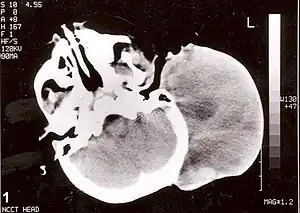

![]() | |

| Non-contrast CT scan of head showing a large mass without any intracranial extension. The diagnosis was post-auricular congenital alveolar rhabdomyosarcoma. | |